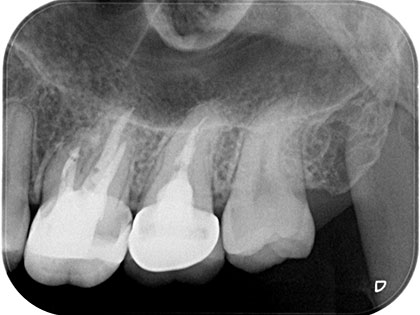

• 術前の写真がこちら

• 歯根端切除の術前5